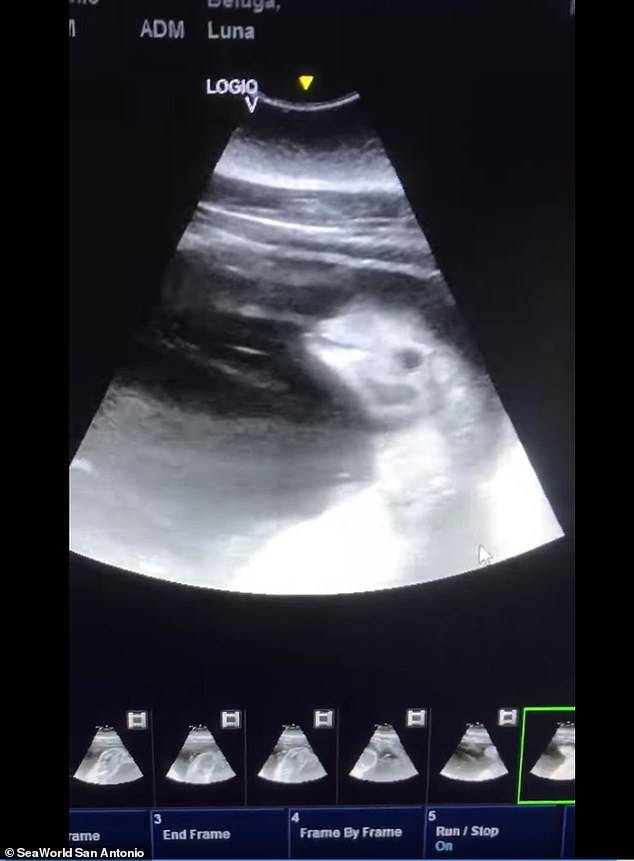

미국의 한 해양테마공원 측이 흰고래로도 불리는 벨루가 암컷 한 마리가 임신했다는 소식을 전하며 어미 배 속에서 새끼가 움직이고 있는 모습을 담은 보기 드문 초음파 영상을 공개해 화제다.

KSAT 등 현지매체 보도에 따르면, 텍사스주(州) 관광명소 '시월드 샌안토니오 지점'은 지난 11일(현지시간) 페이스북을 통해 암컷 벨루가 루나(Luna)의 배 속 태아를 촬영한 초음파 영상을 공개했다.

영상은 태아 상태의 새끼 벨루가가 움직일 때마다 그 머리와 눈 그리고 상반신 일부가 나타나는 모습을 담고 있다.

이에 대해 공원 측은 “어미는 ‘허즈번드리 트레이닝’(husbandry training)으로 불리는 특수 훈련을 받은 덕분에 수의팀이 검사하는 동안 가만히 있을 수 있어 초음파 영상을 기록할 수 있었다”고 설명했다. 허즈번드리 트레이닝은 동물원 등에서 멸종 위기에 처한 동물 등을 보존하기 위한 노력의 일부분으로 행하는 훈련 방법을 말한다.

공원 측은 또 “우리는 루나의 임신 소식을 공유하게 돼 매우 기쁘고 앞으로 새끼 벨루가를 시월드 가족으로 맞이할 날을 기대하며 어미를 24시간 내내 보살필 계획”이라고 밝혔다. 초음파 영상 속 새끼 벨루가는 오는 가을쯤 태어날 예정이다.